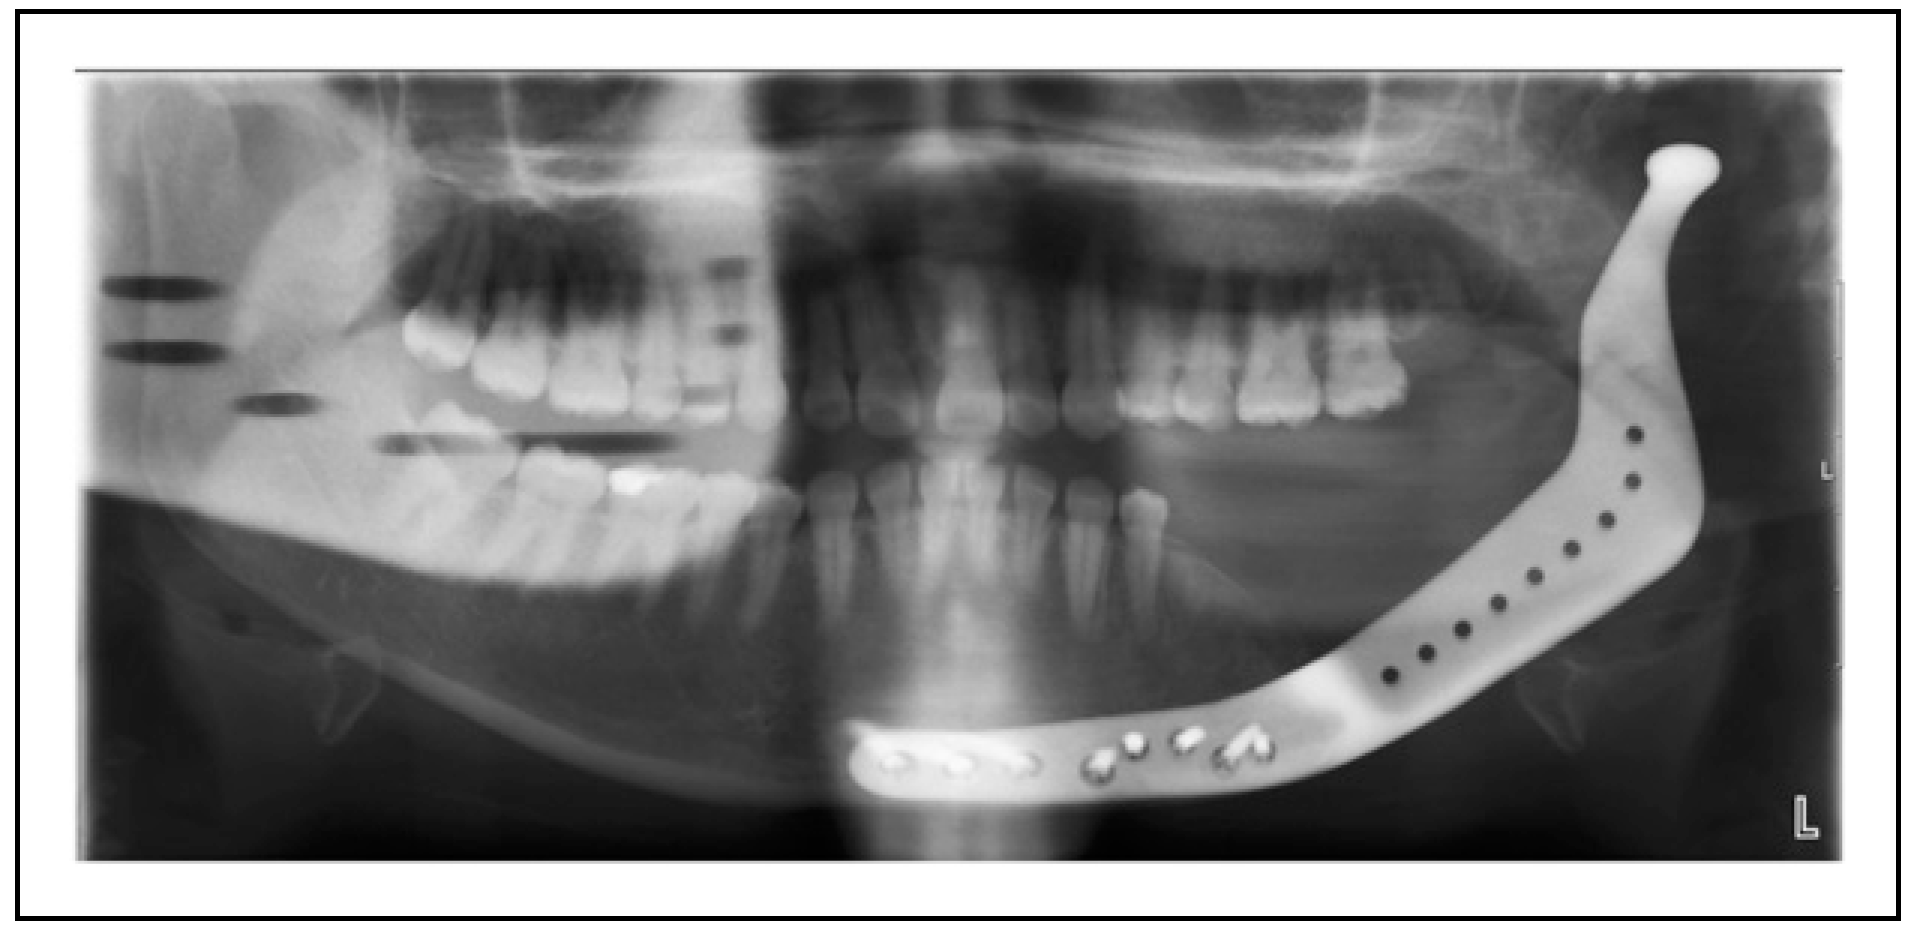

Bilateral TMJ Replacement With Complete Replacement of the Mandible, Patient 8